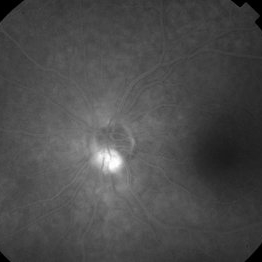

Disseminated Chorioretinitis With Unknown Etiology

Disseminated Chorioretinitis With Unknown Etiology

Apr 5 2018 by Kim Barrett

Ultra-wide field fluorescein angiogram of a 31-year-old female with intermittent pain in her left eye. Her condition has been managed in Liberia until recently when she moved to the United States. She suffers from multiple modalities including central retinal artery occlusion, posterior synechiae of the iris, interstitial keratitis, disseminated chorioretinitis, as well as HIV. An infectious cause is high on the differential in light of her HIV status. DDx: hypertensive crisis, an embolism (? IV drug use), coagulopathy, trauma, infectious. Blood work was normal. Her current vision is 20/30 right eye and 20/400 left eye.

Photographer: Kim Barrett, COA

Imaging device: Optos

Condition/keywords: central retinal artery occlusion (CRAO), chorioretinal scar, ciliary artery sparring, disseminated chorioretinitis, HIV, left eye, optic atrophy, staining